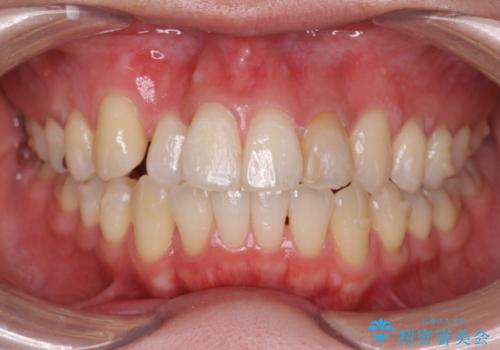

引っ込んだ前歯を並べたい マウスピースと部分ワイヤーのコンビネーション矯正

- 引っ込んで生えてしまっている前歯を並べたい、と矯正治療を希望され来院されました。

まずマウスピース矯正インビザラインシステムで、引っ込んだ歯が並ぶためのスペースを作ったのち、部分ワイヤー矯正を行い短期間での配列を計画します。

このように前歯の部分ワイヤーは引っ込んでしまった前歯や がたつきを素早く改善することができます。